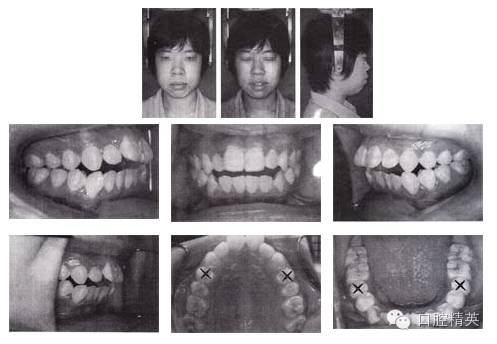

姓名:蘇某 年齡:18歲 性別:女

主訴:口唇前突、開頜,求矯治。

檢查:恒牙列,雙側(cè)磨牙中性偏遠中關(guān)系,11、12 、13 、21、22 、23中度開頜,上下頜牙列輕度擁擠。正面觀,面型左右對稱;側(cè)面觀,雙頜前突,明顯開唇露齒,下頜頦部發(fā)育不良致后縮。顳下頜關(guān)節(jié)無異常。

診斷:

①安氏I類錯頜;

②雙頜前突;

③上下頜牙列輕度擁擠;

④前牙中度開頜;

⑤頦部發(fā)育不良致后縮。

圖3-1 矯治前面像及口內(nèi)像(開始矯治 2002-08-25)